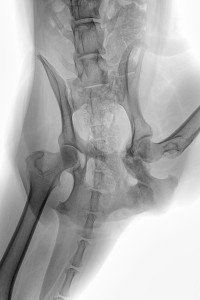

Die Aufnahme vom 04. Nov. zeigte bereits eine beginnende Kallusbildung und mit Absprache des Orthopäden wurde ab dem 03. Dez. mit Physiotherapie, d.h. Unterwasserlaufband begonnen. Fast zeitgleich konnten wir ab Mitte Dez. Ihr Ergodyn VET-Line Gerät zum Einsatz bringen. Die Physiotherapie erfolgte zunächst nur einmal pro Woche, aber das Ergodyn haben wir fast täglich an den Hund angelegt. Beginnend mit 5 Minuten und steigernd auf 15 Minuten.

Auf der RÖ-Aufnahme vom 06. Jan. 2016 ist eine deutliche Kallusbildung an allen Frakturstellen zu erkennen. Wir machten uns allerdings Sorgen, dass es zu einer überschießenden Kallusreaktion am caudalen Bereich des Acetabulums kommen könnte, die dann die Bewegung des Femurkopfes einschränken könnte. Ab Januar wurde die Physiotherapie / Unterwasserlaufband dann zwei Mal wöchentlich durchgeführt und zu Hause mit isometrischen Übungen (wie Trampolin-Wippen, auf 3 Beinen stehen, Podesttraining usw.) begonnen, um die immer noch schwachen Oberschenkelmuskeln zu trainieren. Gleichzeitig haben wir das Ergodyn Gerät jeden zweiten Tag eingesetzt, mit längerer Anlegezeit (ca. 15-20 Min.).